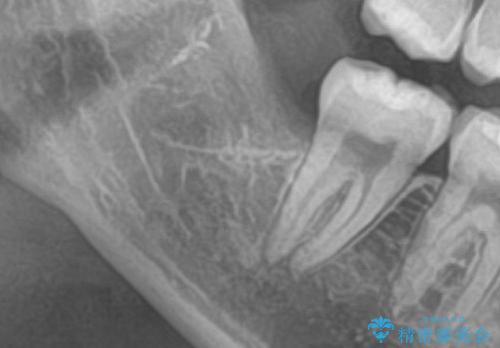

レントゲンで親知らずが埋伏していたため抜歯術を行いました。

下顎には下歯槽神経が通っていて傷つけてしまうと麻痺が起こってしまう可能性があるため、CTを撮り、安全を確認しながら抜歯を行っています。